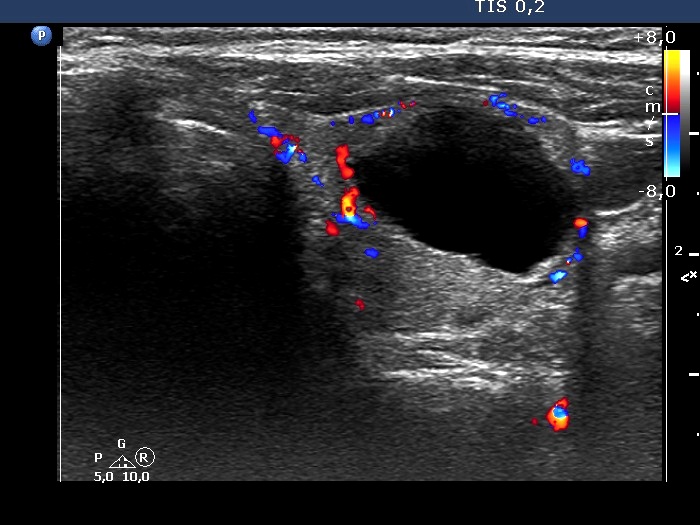

Right lobe, longitudinal scan

Left lobe, transverse scan, color Doppler mode. The lesion has perinodular blood flow.